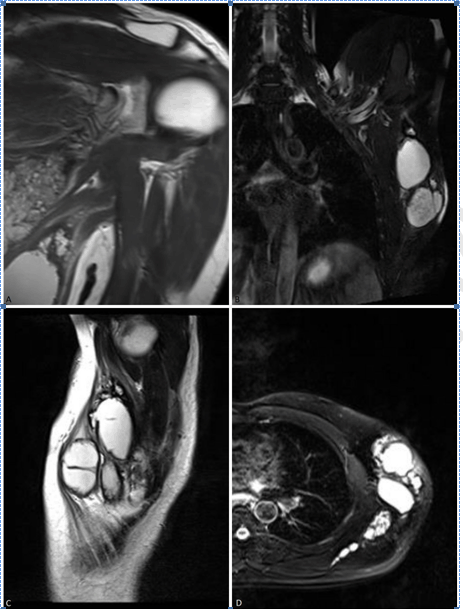

A 30-year-old man, a taxi driver, presented with a large painless, slowly growing mass in his left armpit for approximately three years. He was diagnosed in the same location with an axillary hydatid cyst four years ago and was surgically treated. He also had a history of a successful craniotomy when he was nine years old due to CHD, but no document to support it. Physical examination revealed a 20x8 cm dense, semi-mobile painless mass in the left axillary fossa and conserved range of motion in the left glenohumeral joint Serology test (ELISA) for Echinococcosis was positive. MRI scan showed a large multicystic intramuscular mass in inferior tip of the left scapula and in the dorsal thoracic muscles invading the deltoid, infraspinatus, teres major and teres minor muscles as shown in Figure 1. CT scan and sonography for whole body did not show any other involvements. The diagnosis was relatively easy; by his past medical history, imaging data and endemic context. The patient was given albendazole preoperatively for three months. Under general anesthesia, en bloc resection was successfully performed. The specimen was macroscopically two pieces of creamy brown colored membranous soft tissue and multiple small cysts. The membranous tissues were each measuring 23×9×6 cm and 8×4.5×0.5 cm. The cysts measured 1 to 1.7 cm in diameters. Microscopically, cystic walls composed of inner germinal layer and outer fibrous laminar (chitinous) layer surrounded by fibrous capsule. Daughter cysts and protoscolices were also seen. Figure 2 indicates sagittal section of the MRI through the lesion. The images are compatible with type CE2 of the cyst according to WHO classification appearing as honeycomb pattern. The patient was sent home with adjunctive albendazole chemotherapy (15 mg/kg/day) for three months. | ||||||